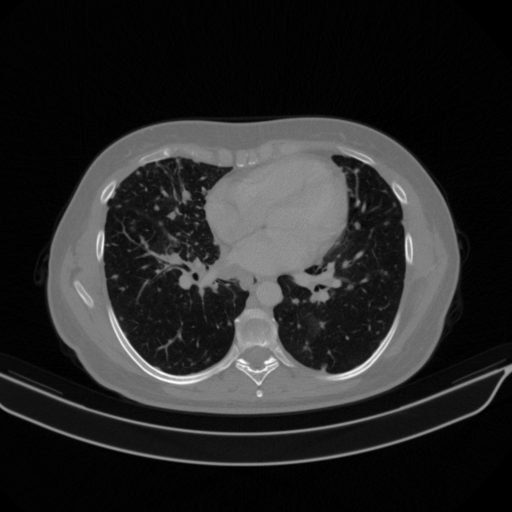

Targeted Slice 70 - Lung Window Analysis (Generated vs Real Venous)

0.752

Lung SSIM

110.9

Lung RMSE

46.5

Lung MAE

Average Lung Window Metrics Across All Slices (133 slices) - Generated vs Real Venous

0.749

Lung SSIM (Avg)

109.7

Lung RMSE (Avg)

44.6

Lung MAE (Avg)

Original NATIVE CT scan (input)

No window - Raw intensity values

Lung window (WL -600, WW 1500 β†’ Low βˆ’1350, High +150)

Mediastinum window (WL 40, WW 400 β†’ Low βˆ’160, High +240)